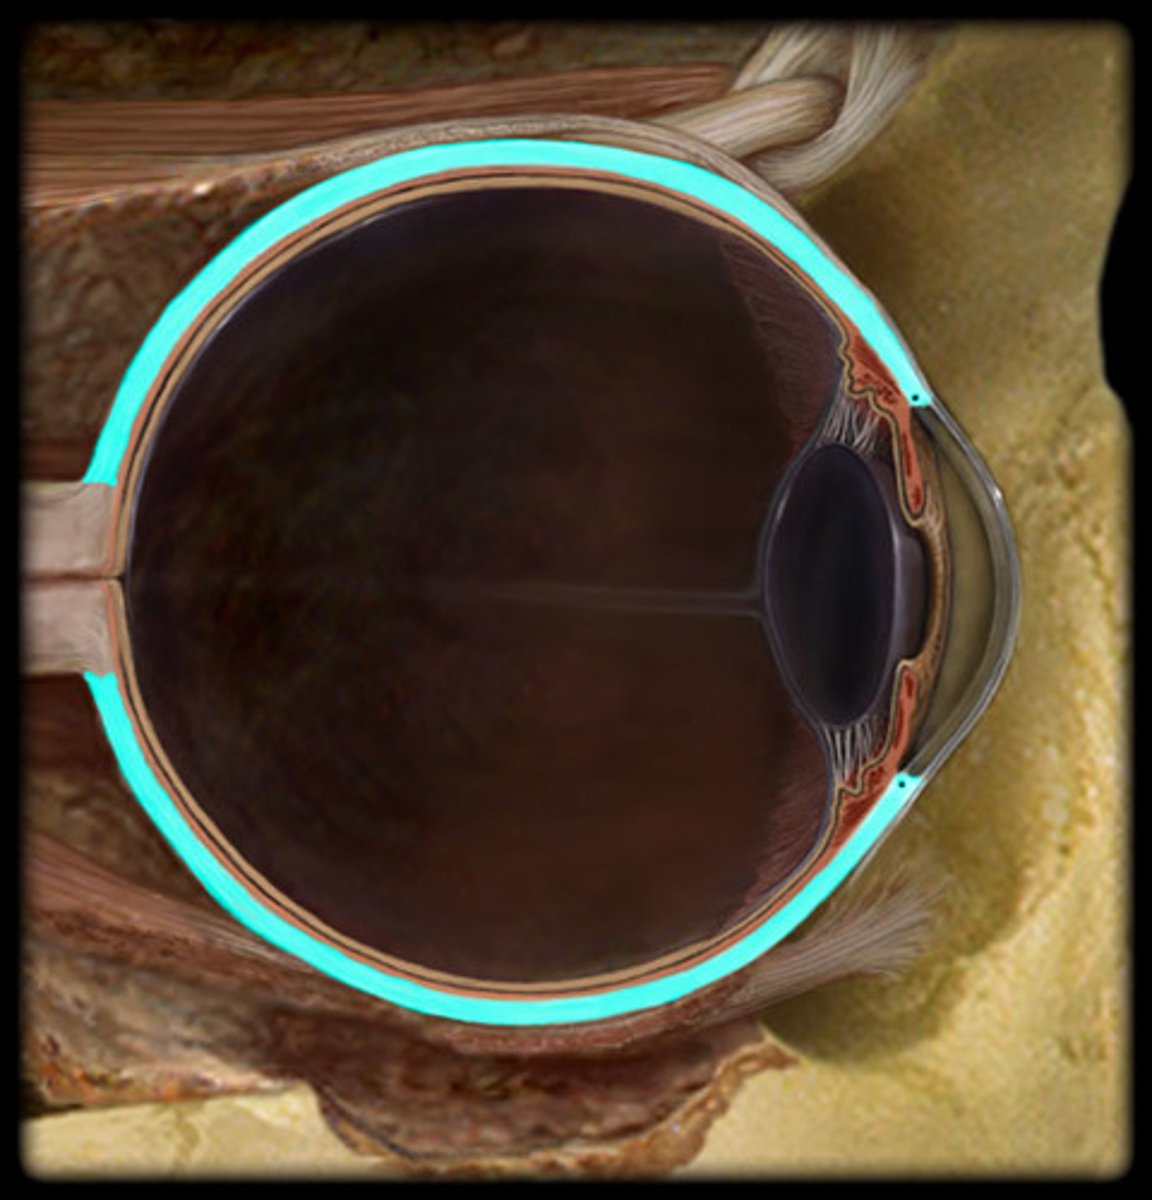

choroid

Sclera

Retina